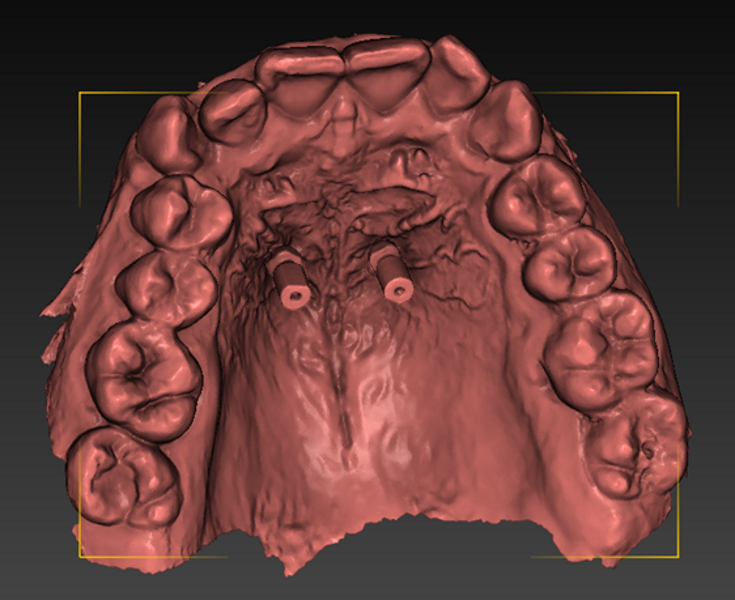

DDS-Pro enables precise planning, guided implantation and appliance design in orthodontics by integrating CBCT data and intra-oral scans into a streamlined digital workflow. (All images: Polorto)

1. capture and analysis of the CBCT scan and intra-oral scan to determine optimal mini-implant placement in line with anchorage needs and appliance design;

2. creation of surgical guides for precise implantation;

3. fabrication of the appliance for installation immediately after implantation; and

4. implantation and appliance installation using a 3D-printed guide.